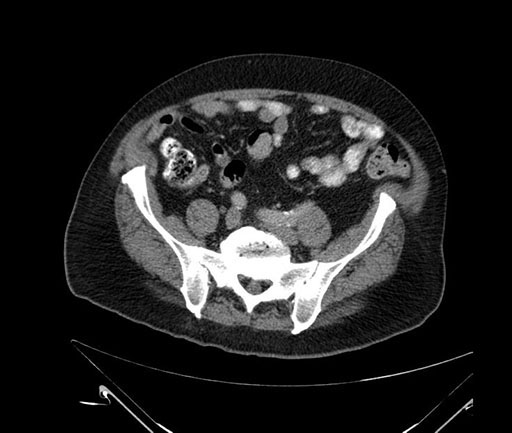

Whipple (pancreaticoduodenectomy) [case 7]

Imaging Analysis

Look through the patient's CT scan to identify any areas of concern for the necessary procedure.

Coronal - stented